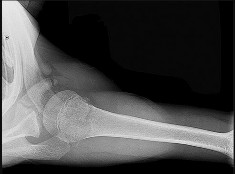

A patientâs upper extremity radiographs are shown in and . What is the most likely inheritance pattern of this condition:

Explanation

characteristic bowing deformity of the forearm and pseudo-Madelung deformity of the wrist are also present.

Multiple hereditary exostoses is autosomal dominant. The putative tumor suppressive gene mutation is EXT1, EXT2. The risk of low-grade chondrosarcoma occurring is approximately 10%.

In most patients, the forearm deformity does not cause a major problem and can be treated nonoperatively. Correct Answe Autosomal dominant